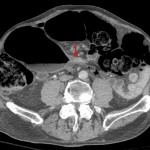

Indication: Altered mental status, abdominal distension

- Large bowel is distended with gas and formed stool from the cecum to the sigmoid colon with apparent transition point in the distal sigmoid colon

- Sigmoid colon is redundant, but does not take the expected configuration of sigmoid volvulus

- Abnormal bowel rotation with reversal of the usual SMA/SMV relationship

- Large bowel obstruction

Findings concerning for large bowel obstruction with possible transition point in the distal sigmoid colon, which could represent a stricture (including neoplastic and inflammatory etiologies) or recently devolvulized bowel segment. No evidence of volvulus or vascular compromise at this time. Of note, the patient appears to have abnormal bowel rotation, which may predispose to volvulus.